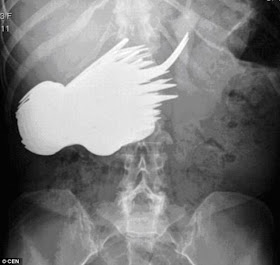

3. Old Dutch woman who swallowed 78 cutlery items

Surgeons were flabbergasted when X-rays showed 78 items of cutlery in 52-year-old, Margaret Daalman’s stomach. After seeing her scan the estate agent’s secretary who had been complaining of belly ache, said: “I don’t know why but I felt an urge to eat the silverware – I couldn’t help myself.”